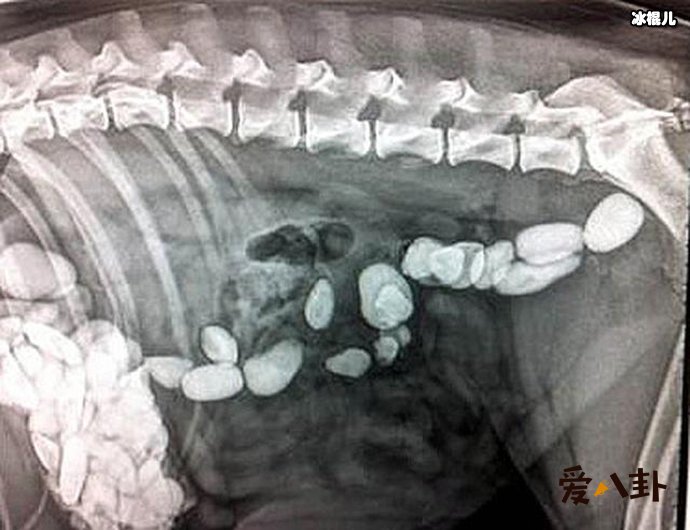

但是小柯的回答让医生也吓了一跳,他回答称:因为自己与女朋友吵架,在吃金项链之前,还赌气吃了200颗的褪黑素下去。这可让医生吓了一跳,马上安排给小柯做相关的检查,发现金项链已经到了肠子里了,而小柯也没有什么不舒服的地方。因此,医生表示金项链会随着大便一起排出,建议小柯在回家排便的时候注意看一下金项链有没有排出。

很多网友对此也纷纷表示,现在的年轻人吵个架起来真是不得了,还表演“吞金”?这样子是真的很容易闹出意外,这次小柯没什么事也算是他的幸运了。医生还表示,其实这并不是少见了,此前有一些想要自杀的患者还吞食过打火机、硬币、玉佩等诸如此类的东西,小柯的金项链与这些一比,还真的是小儿科了。